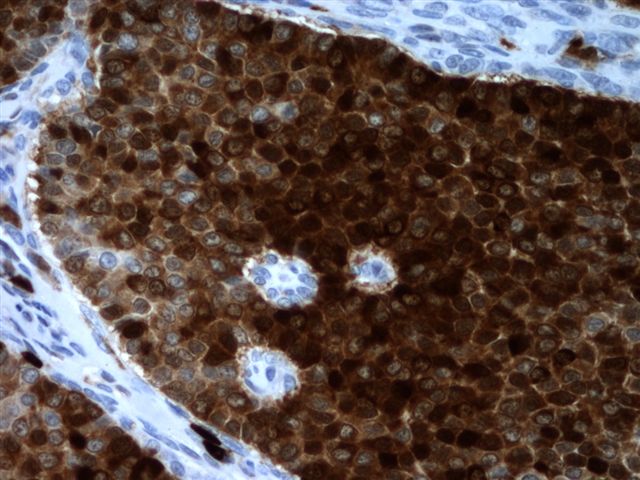

Microscopic (histologic) images

Contributed by Shabnam Zarei, M.D. and Sharon Bihlmeyer, M.D.

AFIP images

Positive stains

- FOXL2 immunostain is a sensitive (80%) and specific (99%) marker for sex cord stromal tumors (SCST), superior to α inhibin and calretinin and is positive in almost all SCST (98%) with FOXL2 mutation and a large number of those without mutation (67%); majority of adult GCTs (93%) are positive with FOXL2 stain and the immunostain cannot differentiate adult GCT from other SCSTs (Am J Surg Pathol 2011;35:484)

- SF1: most sensitive marker for this as well as most common sex cord stromal tumors (Am J Surg Pathol 2009;33:354)

- Inhibin A: more specific marker

- Calretinin (Am J Surg Pathol 2002;26:1477)